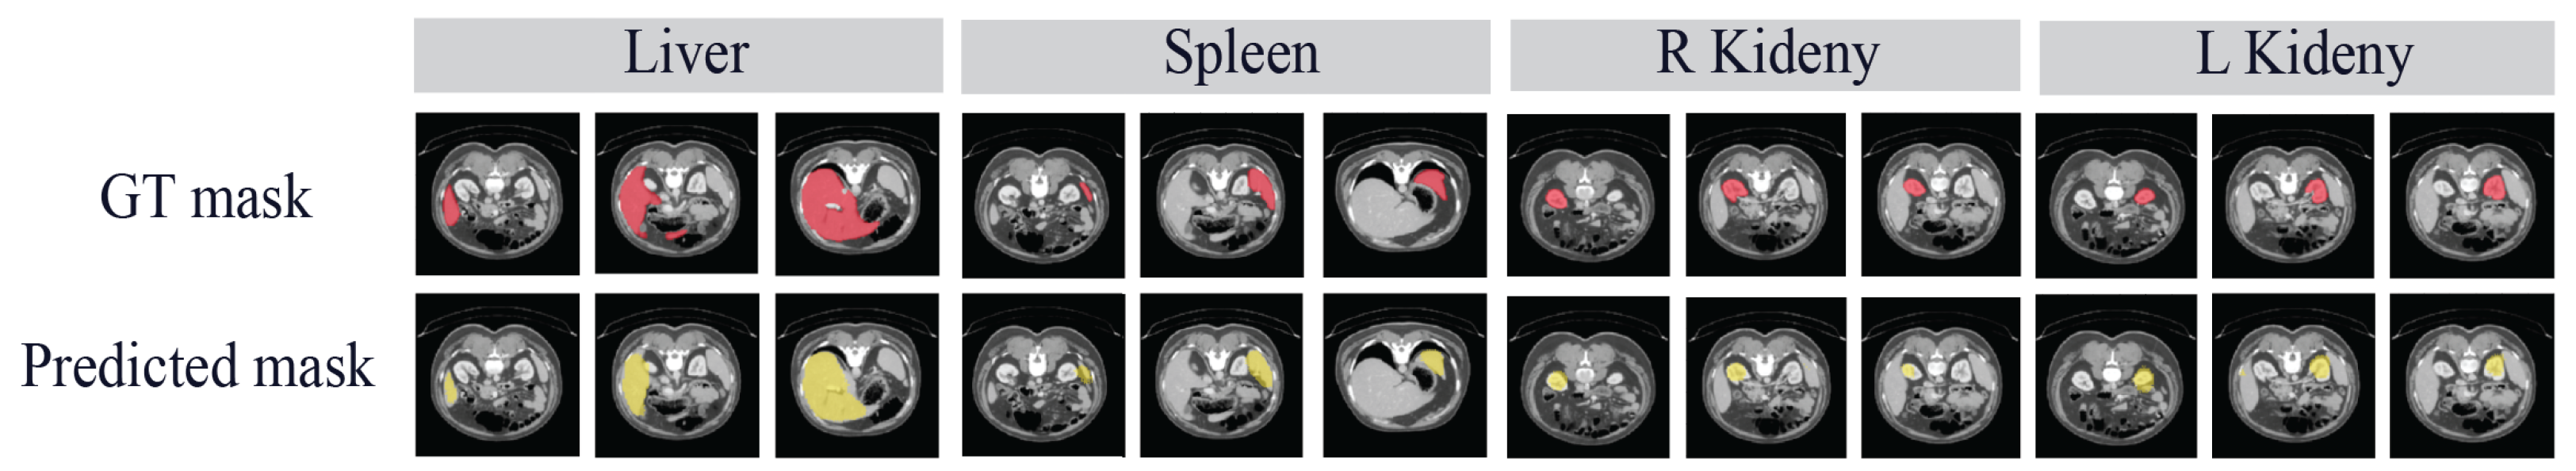

5.5.2. Evaluation on the Hospital Dataset

| Metric | Liver | Spleen | R Kidney | L Kidney | Mean |

|---|---|---|---|---|---|

| DSC | 90.62 | 79.86 | 79.87 | 78.21 | 82.14 |

| IoU | 84.18 | 72.45 | 71.75 | 71.27 | 74.91 |

| HD | 7.77 | 6.84 | 14.85 | 9.88 | 9.84 |